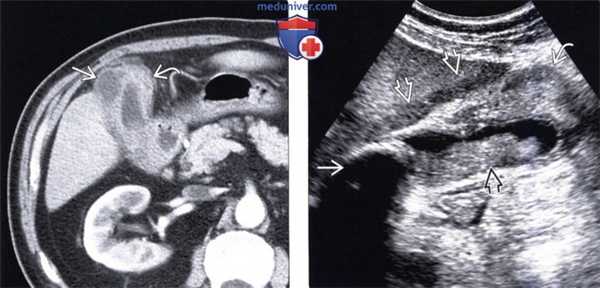

(Справа) На аксиальной КТ с контрастным усилением определяется утолщение стенки желчного пузыря, особенно выраженное в области его дна, граница между желчным пузырем и печенью нечеткая. Несмотря на то, что эти изменения подозрительны на рак желчного пузыря, при холецистэктомии был обнаружен ксантогранулематозный холецистит. (Слева) На аксиальной КТ у пациента с жалобами на боль в правом подреберье определяется неравномерное утолщение стенки желчного пузыря, выраженное в значительной степени; видны также несколько включений низкой плотности рядом с желчным пузырем и одно - в его стенке. Гиподенсные интрамуральные узлы при ксантогранулематозном холецистите могут представлять собой как абсцессы, так и ксантогранулемы.

(Слева) На аксиальной КТ с контрастным усилением у мужчины 75 лет без какой-либо симптоматики определяется иррегулярное утолщение стенки желчного пузыря с наличием в ней гиподенсных включений.

(Справа) На сонограмме у этого же пациента определяется асимметричное утолщение стенки желчного пузыря с наличием сладжа в его просвете и конкремента в области шейки. Визуализируется также участок неизмененной жировой ткани. Предоперационная дифференциальная диагностика рака желчного пузыря и ксантогранулематозного холецистита часто бывает сложной, однако отсутствие расширения желчных протоков позволяет предположить скорее хронический воспалительный процесс, а не новообразование.

(Слева) На аксиальной КТ с контрастным усилением у женщины 64 лет с хронической болью в правом подреберье определяется утолщение стенки желчного пузыря и гиподенсные включения в ней. При патоморфологическом исследовании было обнаружено, что эти гиподенсные включения представляют собой зоны некроза, заполненные пенистыми макрофагами. Обратите внимание на усиление перфузии печени (преходящее повышение плотности).

(Справа) На сонограмме у этой же пациентки определяется утолщение стенок желчного пузыря, просвет которого заполнен сладжем, с наличием множественных кистозных участков некроза в передней стенке.